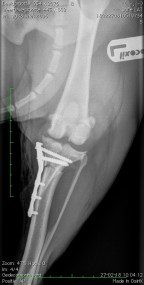

Zijn pootje in dat rare witte spul, zodat hij niet eens met zijn voet de vloer aanraakte. Hij kon zijn pootje ook niet buigen, heel vreemd allemaal. Toen dat er na twee dagen af mocht, had hij een hele kale poot. En dat ging jeuken. Maar daar mocht hij dan weer niet aankomen. Ook al zo raar. Hij hield zich maar rustig zodat er niet nog meer gekke dingen gebeurden. Stel je voor.

Gelukkig ging het twee weken later al een heel stuk beter. Hij ging gezellig met het baasje mee. Even moest hij wel slikken toen hij zag waar ze heen gingen. Weer dat rare gebouw waar het zo bijzonder rook. Hij had er niet zo op. Meestal gebeurden er zo maar akelige dingen als hij daar was. Gelukkig was nu er een hele aardige mevrouw die hem gelijk enthousiast begroette. Ze keek naar zijn kale pootje en knipte wat van de stomme draadjes af die er uit staken. Ze was wel tevreden, geloofde hij. Het baasje lachte dus het zou wel goed zijn.